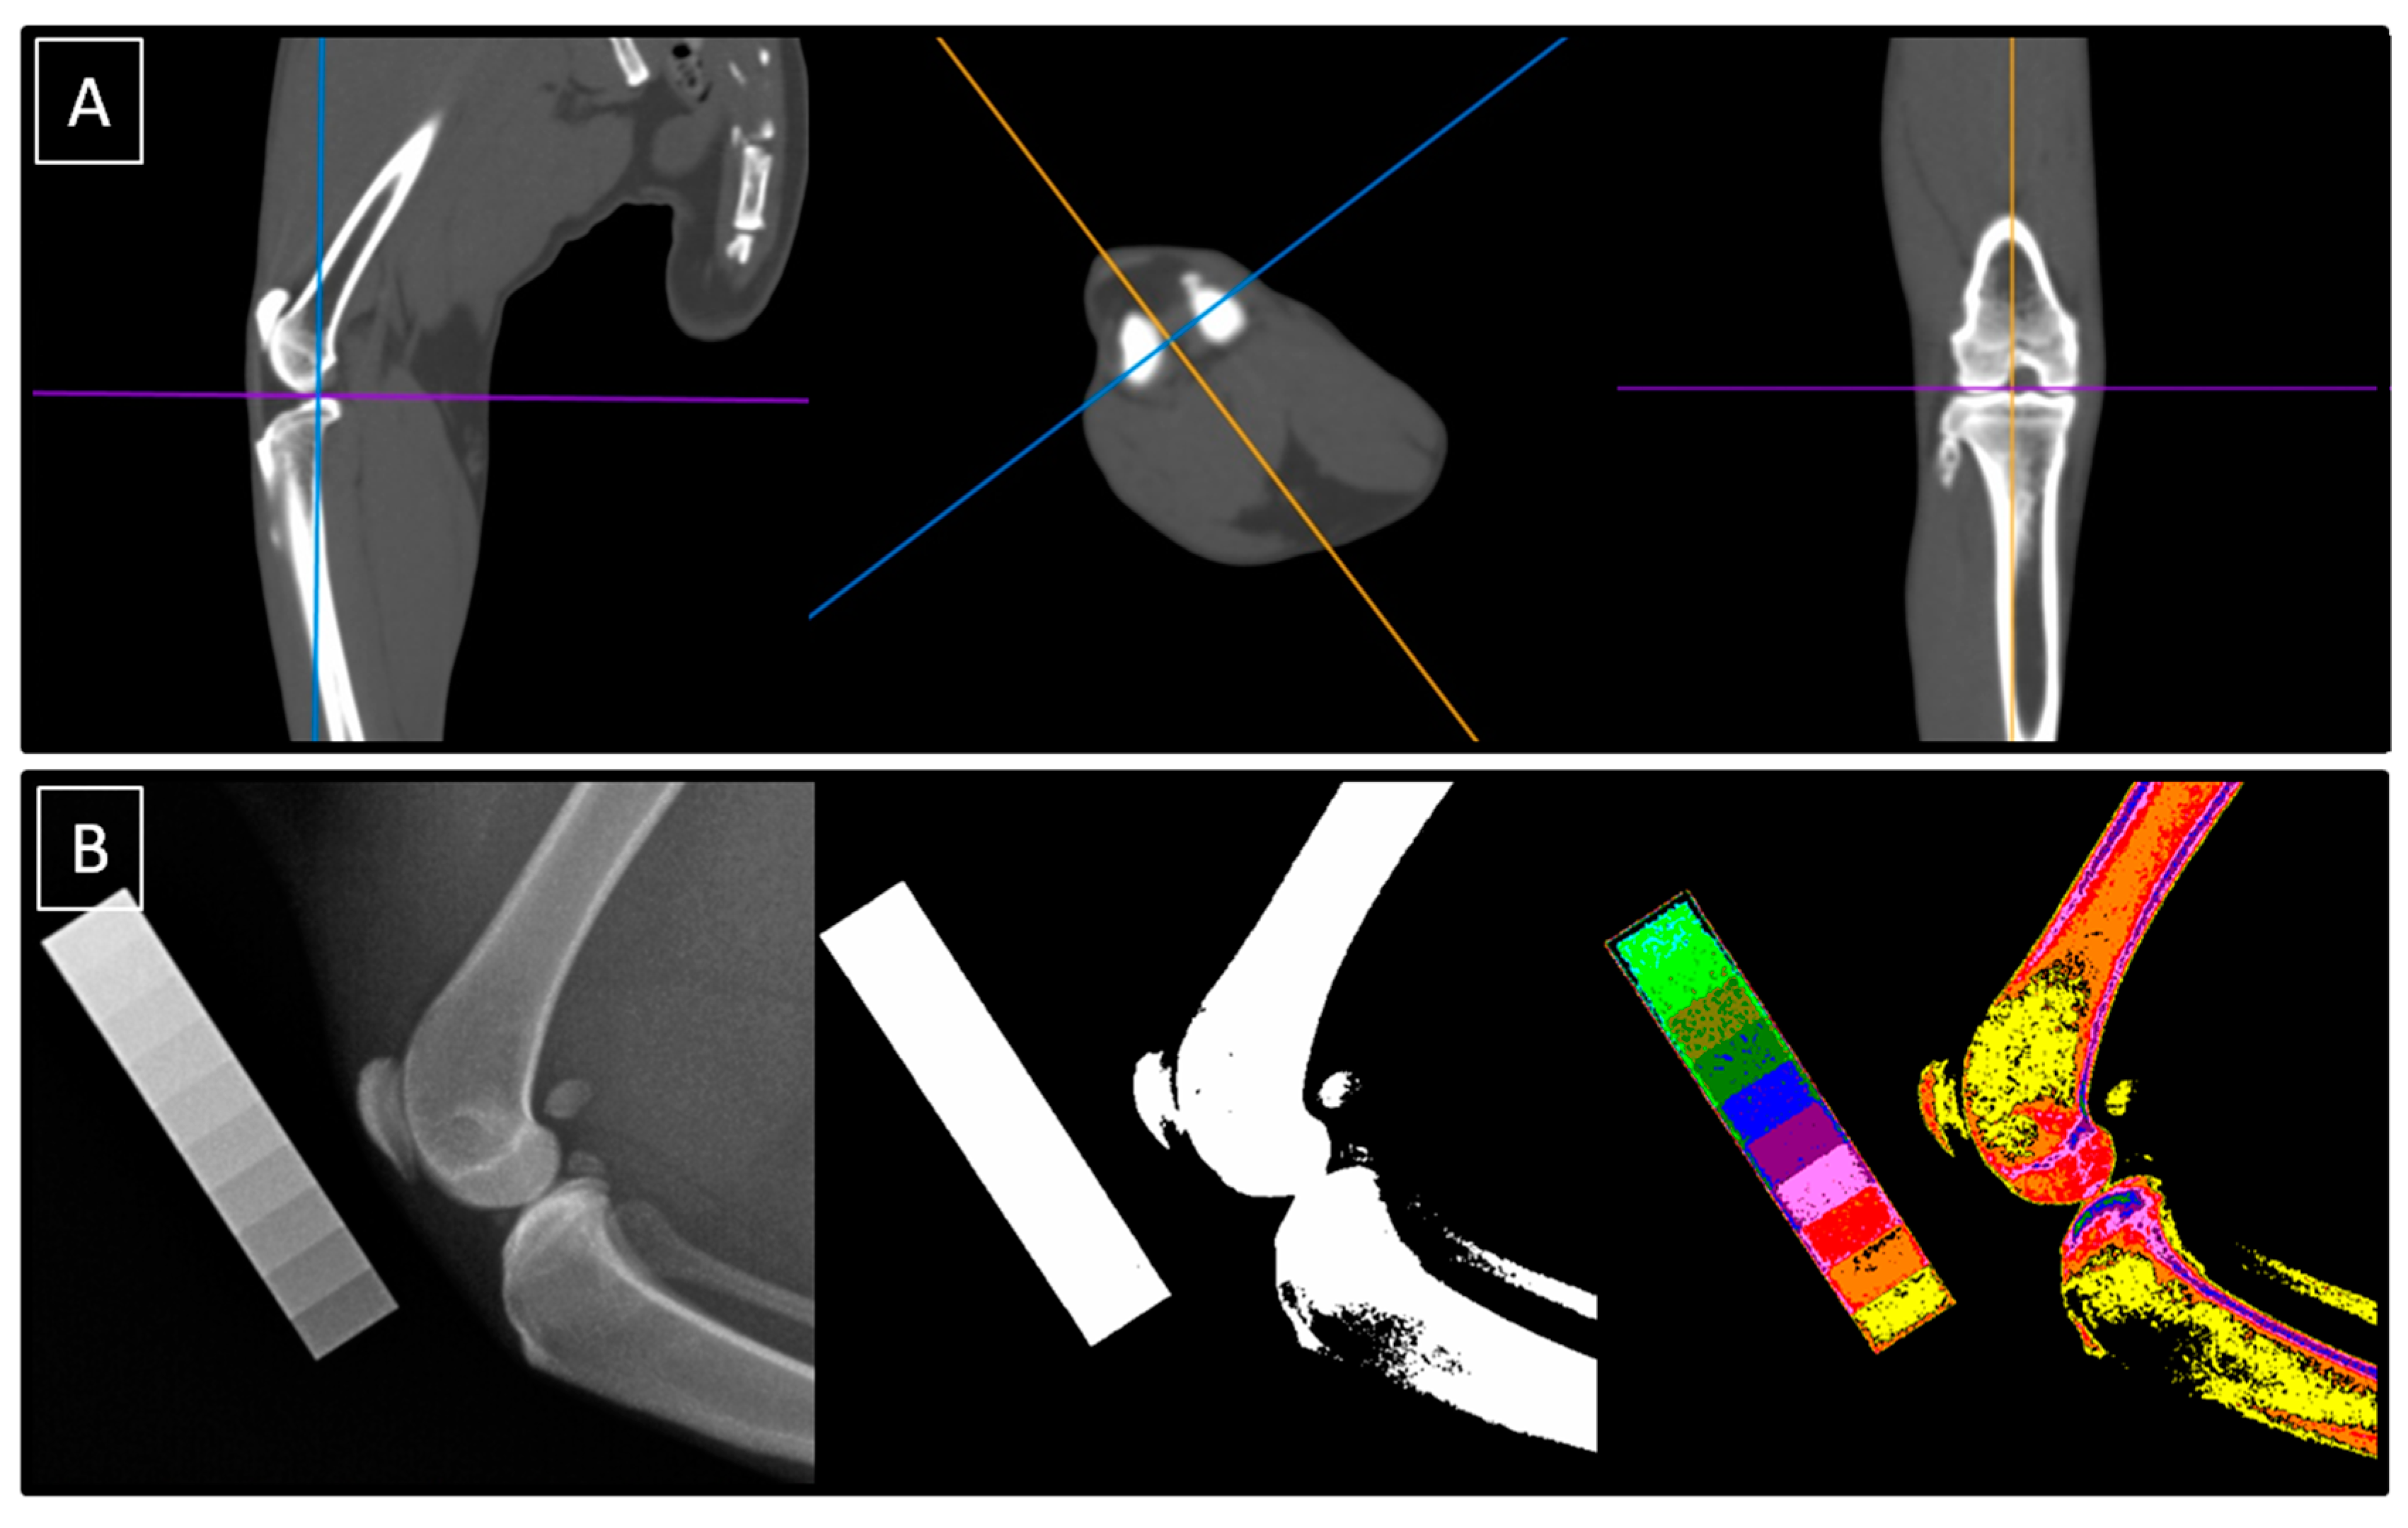

2.2.1. Image Collection Using Computed Tomography

2.4.1. Quantification of Computed Tomography Images

2.4.2. Quantification of Computed Digital Absorptiometry Images